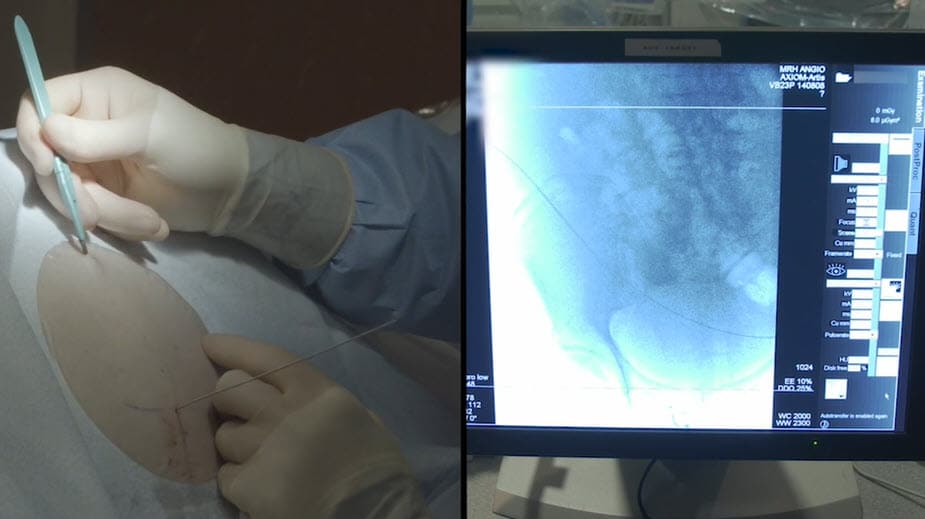

With three placement method options (antegrade, retrograde and over-the-wire), and multiple kit options designed to accommodate customer and patient needs, the Aspira Drainage System gives you more placement flexibility than the PleurX Drainage System.